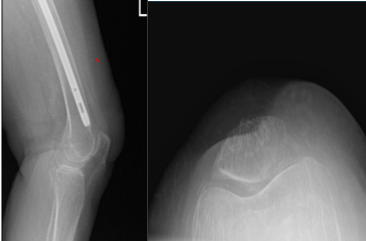

After 6 weeks from the first visit, the patient returned with a CT scan result, it was reviewed and ruled out our impingement, and there were mild degenerative changes of the left hip and presents atherosclerotic disease.

Also found that the distal tip of the femur impinging on the anterior cortex of the femur with erosion. We discussed treatment options including operative and nonoperative treatment.

Left Knee X-ray AP and Lateral with Oblique 3 views